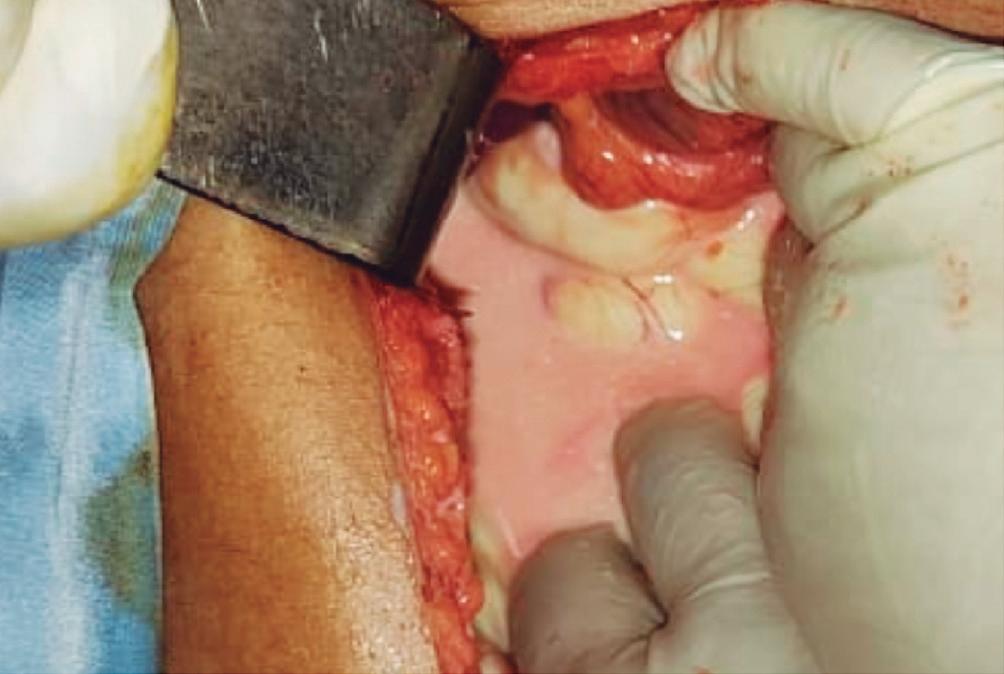

Evaluación endoscópica e histológica

La endoscopía superior es un procedimiento fundamental para el diagnóstico, la evaluación de la respuesta al tratamiento y el monitoreo a largo plazo de la actividad de la EEo. Los hallazgos endoscópicos típicos incluyen edema (reducción de vascularidad), anillos esofágicos fijos, exudados blancos, surcos longitudinales, estenosis, estrechamiento de la luz esofágica, friabilidad de la mucosa (mucosa en papel crepé) y una consistencia firme de la mucosa al realizar biopsias (signo de “tracción" o "resistencia”) en pacientes con fibrosis (Figura 1). Estos hallazgos no son patognomónicos y no constituyen un criterio diagnóstico; sin embargo, cuando se evalúa de forma cuidadosa, en la gran mayoría de los casos se pueden observar.19-21

Un elemento fundamental en la evaluación de la EEo es la aplicación del puntaje de referencia endoscópica para la esofagitis eosinofiílica (EREFS por sus siglas en inglés: Eosinophilic Esophagitis Endoscopic Reference Score).20 El acrónimo EREFS también refleja las cinco características endoscópicas principales de la EEo: Edema, anillos esofágicos (Rings), Exudados, surcos longitudinales (Furrows) y estenosis (Stricture). Estas características se clasifican según su severidad mediante un sistema de puntuación que oscila entre 0 y 9, considerándose la región esofágica con la alteración más marcada. El EREFS cuenta con validación interna y externa, y ha demostrado una elevada capacidad para diferenciar la EEo de otras patologías no relacionadas en poblaciones pediátricas y adultas, además de correlacionarse con la respuesta terapéutica.23-25 Por estos motivos, el EREFS constituye un sistema estandarizado para la evaluación

En el panel A se observa un esófago con edema difuso y pliegues longitudinales; en el panel B se aprecia edema con pliegues y exudados blanquecinos; en el panel C se evidencia un estrechamiento luminal acompañado de anillos esofágicos y exudados; y en el panel D se muestra un desgarro mucoso posterior a la dilatación con bujía de Savary, hallazgo esperado tras este procedimiento terapéutico.

Figura 1. Características endoscópicas de la esofagitis eosinofílica